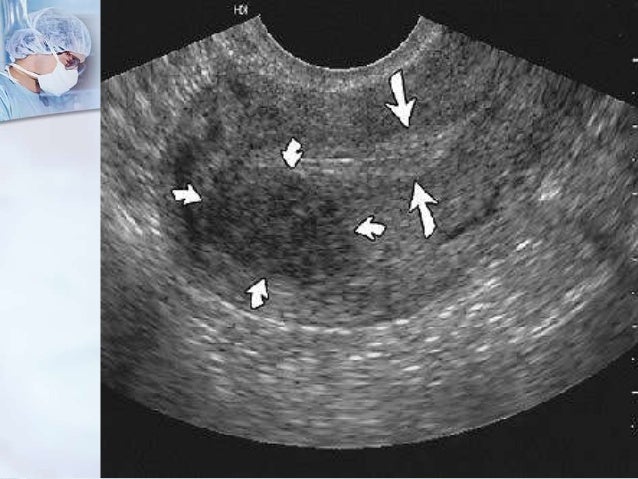

Медицинская диагностика: Гиперплазия эндометрия на УЗИ

Раздел: Мудрость в объективе